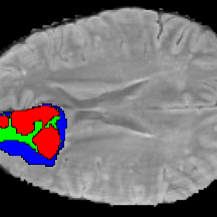

Current research on deep learning for medical image segmentation exposes their limitations in learning either global semantic information or local contextual information. To tackle these issues, a novel network named SegTransVAE is proposed in this paper. SegTransVAE is built upon encoder-decoder architecture, exploiting transformer with the variational autoencoder (VAE) branch to the network to reconstruct the input images jointly with segmentation. To the best of our knowledge, this is the first method combining the success of CNN, transformer, and VAE. Evaluation on various recently introduced datasets shows that SegTransVAE outperforms previous methods in Dice Score and $95\%$-Haudorff Distance while having comparable inference time to a simple CNN-based architecture network. The source code is available at: https://github.com/itruonghai/SegTransVAE.